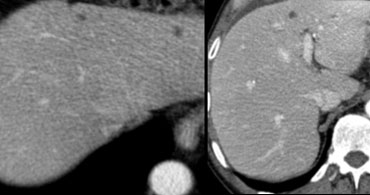

Aspecific hypovascular lesion on CT Aspecific hypovascular lesion on CT

On the left an atypical, apparently hypovascular lesion on CT, possibly metastasis.

MR depicts enhancement better than CT MR depicts enhancement better than CT

Same case on dynamic MR.

Notice how MR depicts the nodular, peripheral, slowly progressing enhancement (blue curved arrow) which CT failed to depict.